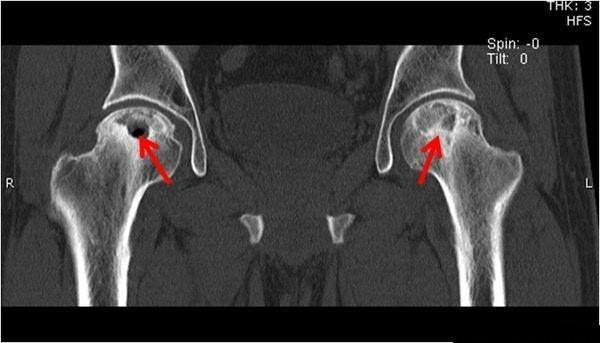

ct可见股骨头硬化,囊状.

髋关节骨囊肿

关节面塌陷变扁,关节间隙狭窄,髋臼出现坏死变化,囊性变,囊肿和骨刺Ⅳ